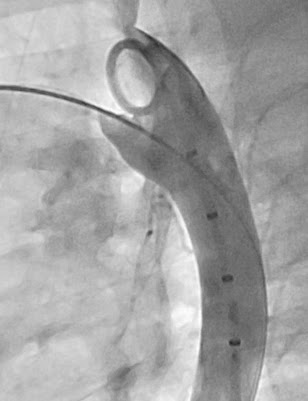

Bilindiği gibi artık PDA’ların bir çoğu ameliyatsız kapatılabilmektedir. Burada Duct Accluder I tipi cihazın yerleşimi görülmektedir. Bu tip işlemlerin en büyük faydası komplikasyon oranlarının çok düşük olması ve hastanın ertesi gün normal hayatına devam edebilmesidir.

Şekiller: Geniş bir PDA’nın kapatılma öncesi ve sonrası görünümü